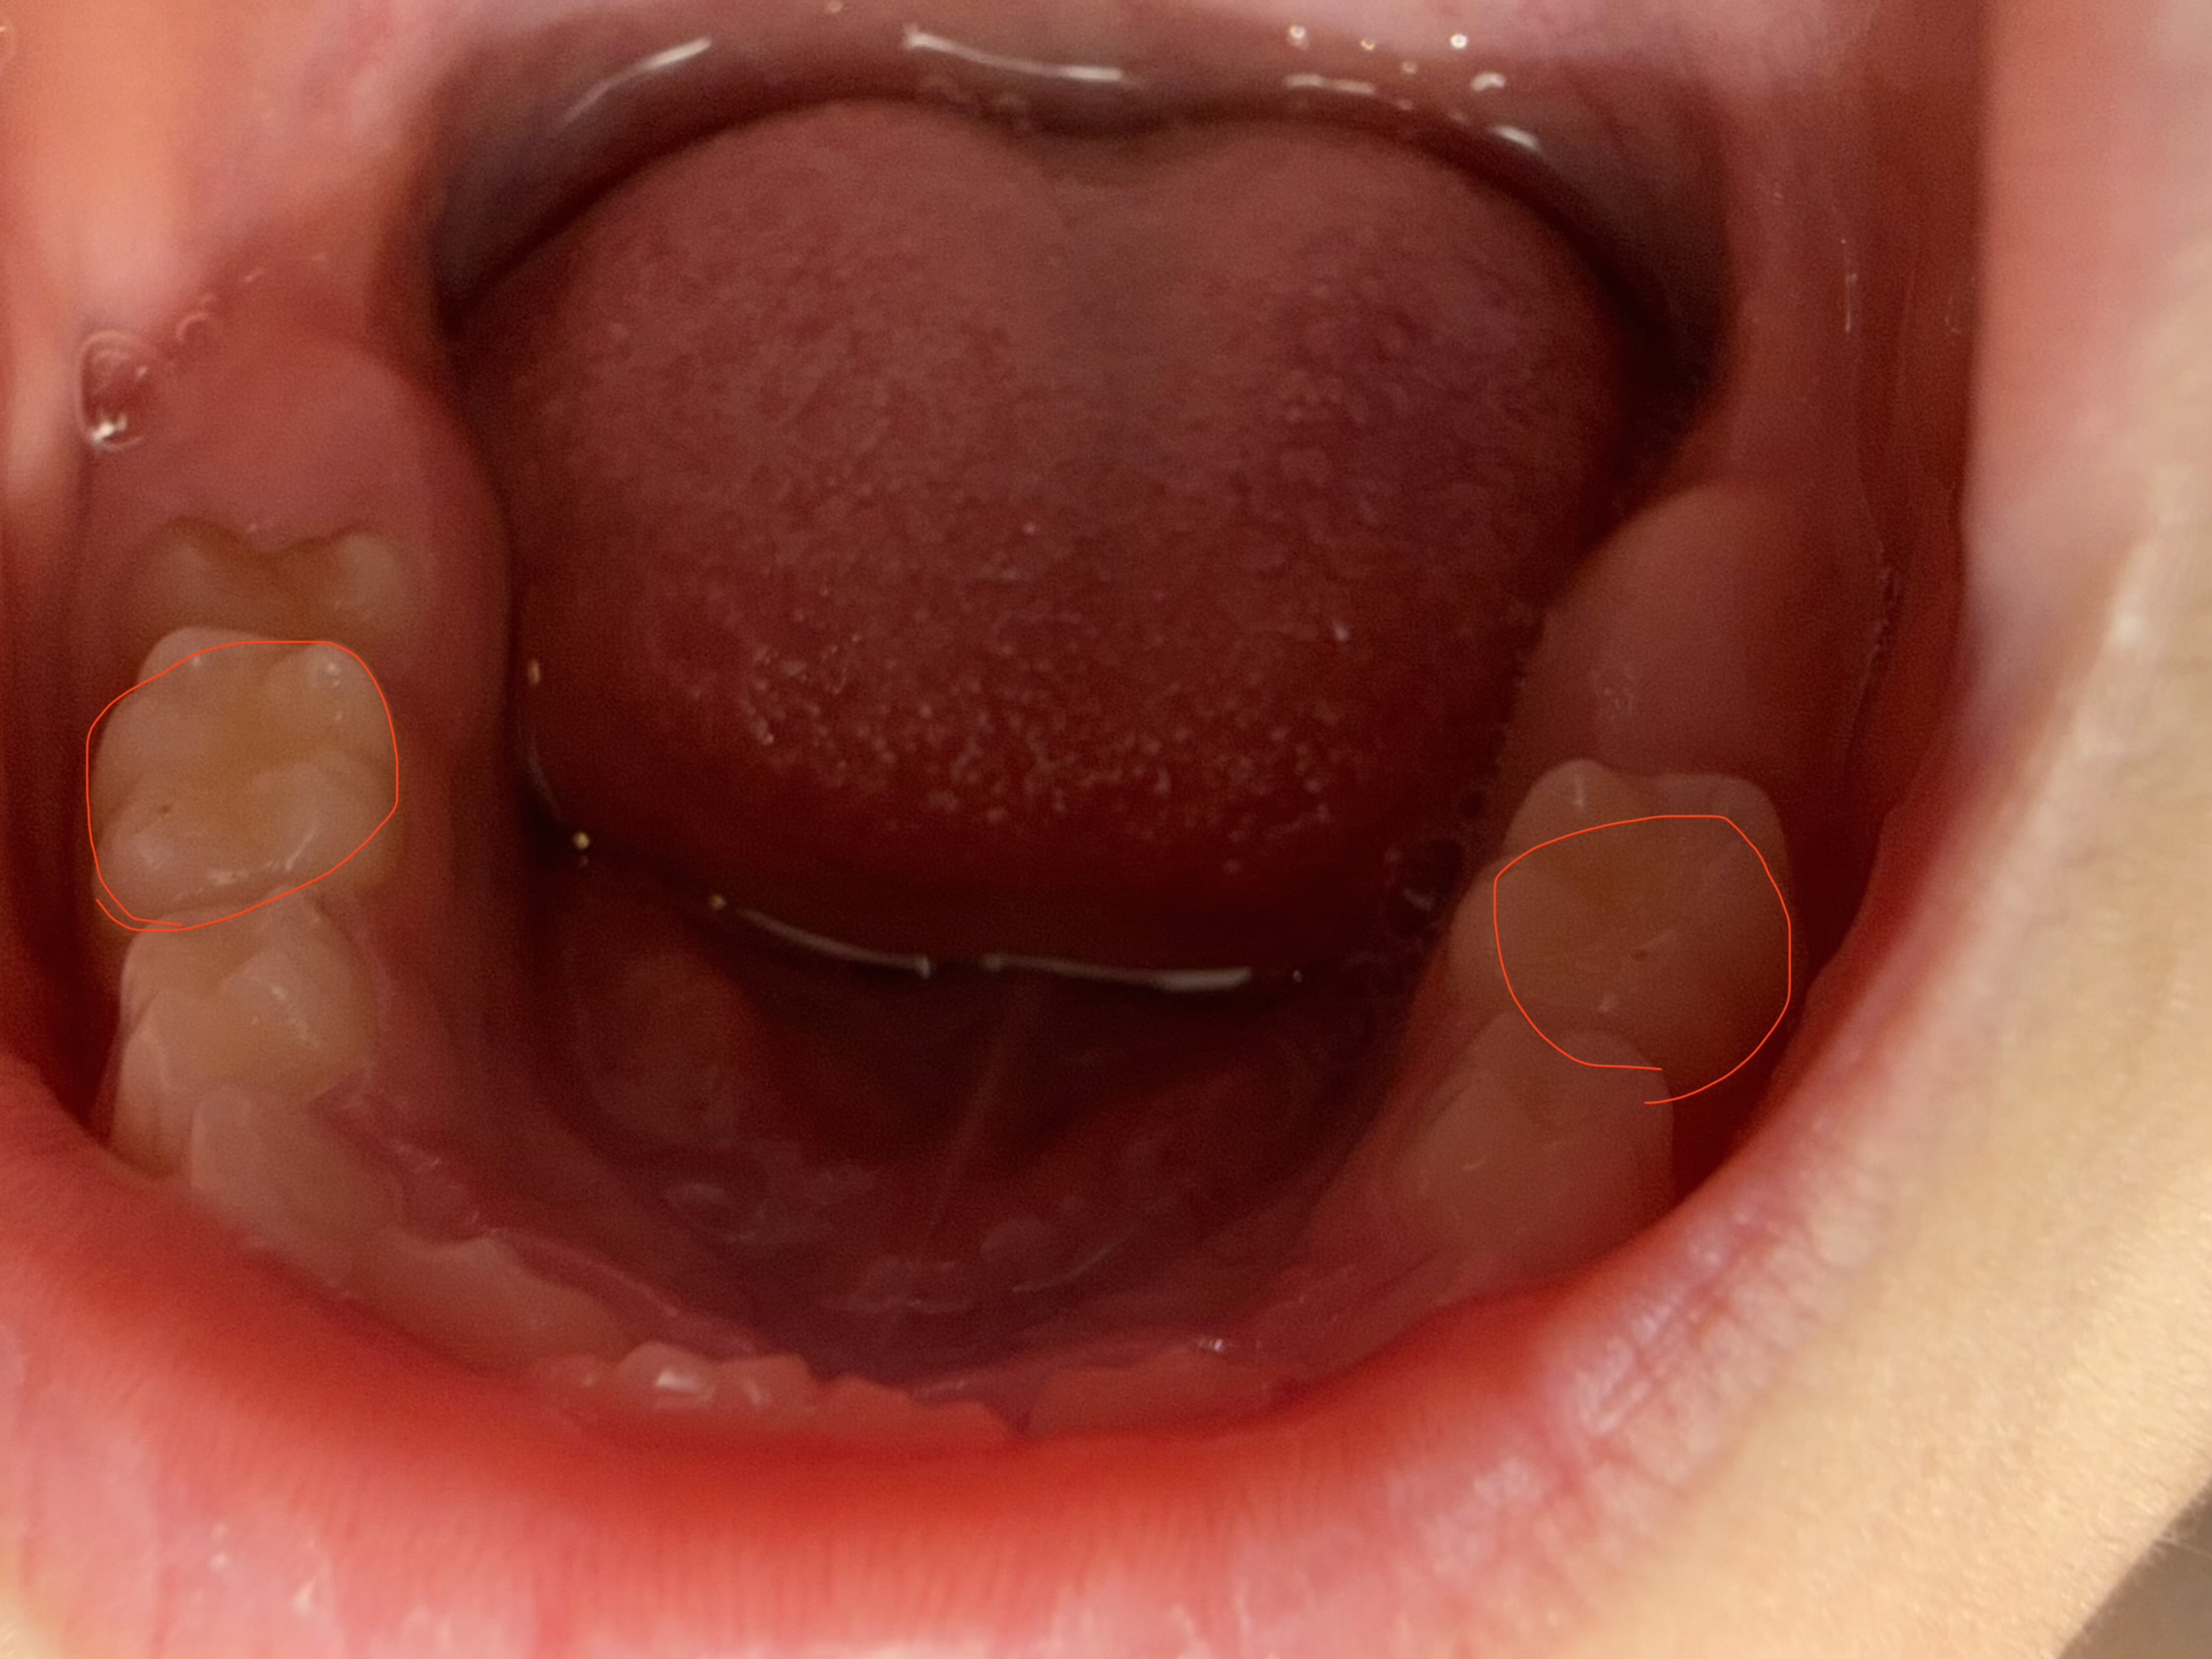

子供の奥歯に茶色い汚れがあります。虫歯でしょうか?

回答数:2